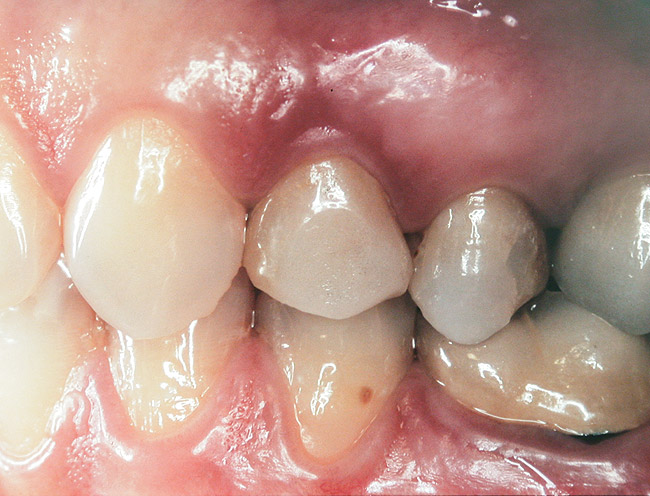

At the time of surgery, the tooth was extracted without harvesting any mucosal flap because the implant site was prepared by means of a pilot drill bur (Figure 13) and alternating osteotomes (Figure 14A and Figure 14B). The implant was positioned and showed primary stability. The implant was loaded 2 days after surgery. Then, splinted PFM crowns supported by custom gold abutments were delivered. At 6 months posttreatment, the radiograph revealed no bone resorption and the clinical result was optimal (Figure 15A and Figure 15B).

Figure 15 A Final implant-supported PFM restorations.

Figure 15a  Final implant-supported PFM restorations.

Figure 15a